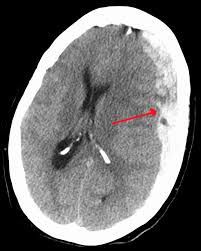

A subdural hematoma is a buildup of blood on the surface of the brain. The blood builds up in a space between the protective layers that surround your brain. Your brain sits within a bony skull. Inside your skull and over the brain there are 3 layers called the meninges.